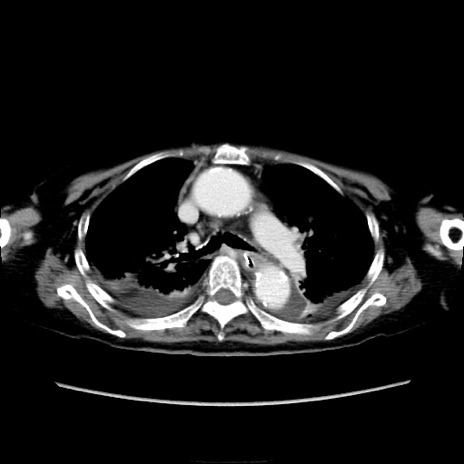

症例40(横断像)

他院CT

横断像